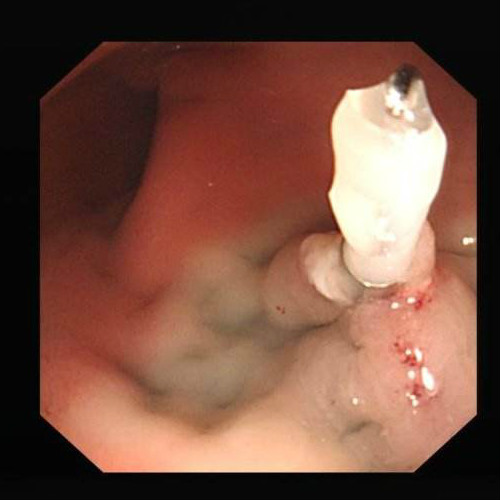

腫瘤性息肉

腫瘤性息肉圖的片